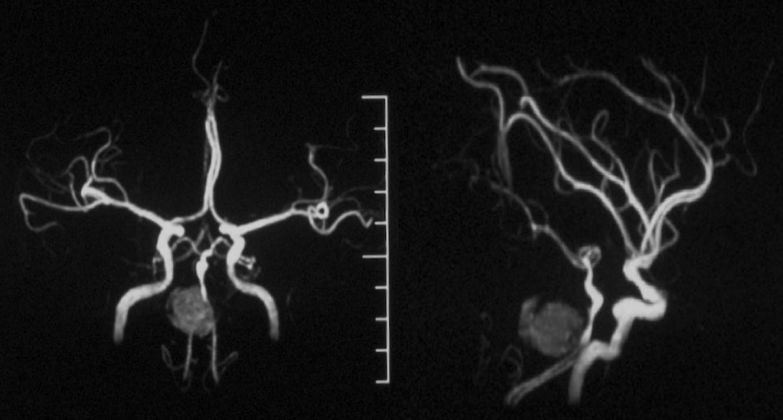

当地医院MRA:基底动脉中上段夹层动脉瘤(2019-09-16)(图5)。

图5

本院 DSA三维血管重建(2019-10-10)显示:基底动脉巨大夹层动脉瘤(图7)。

图7